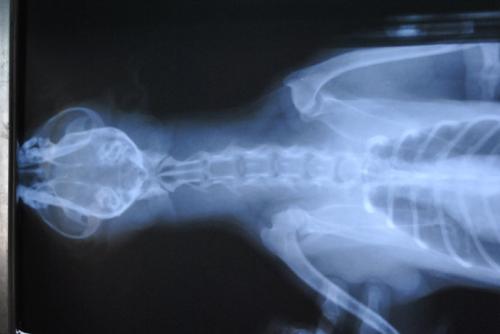

急性脊髓炎的症状